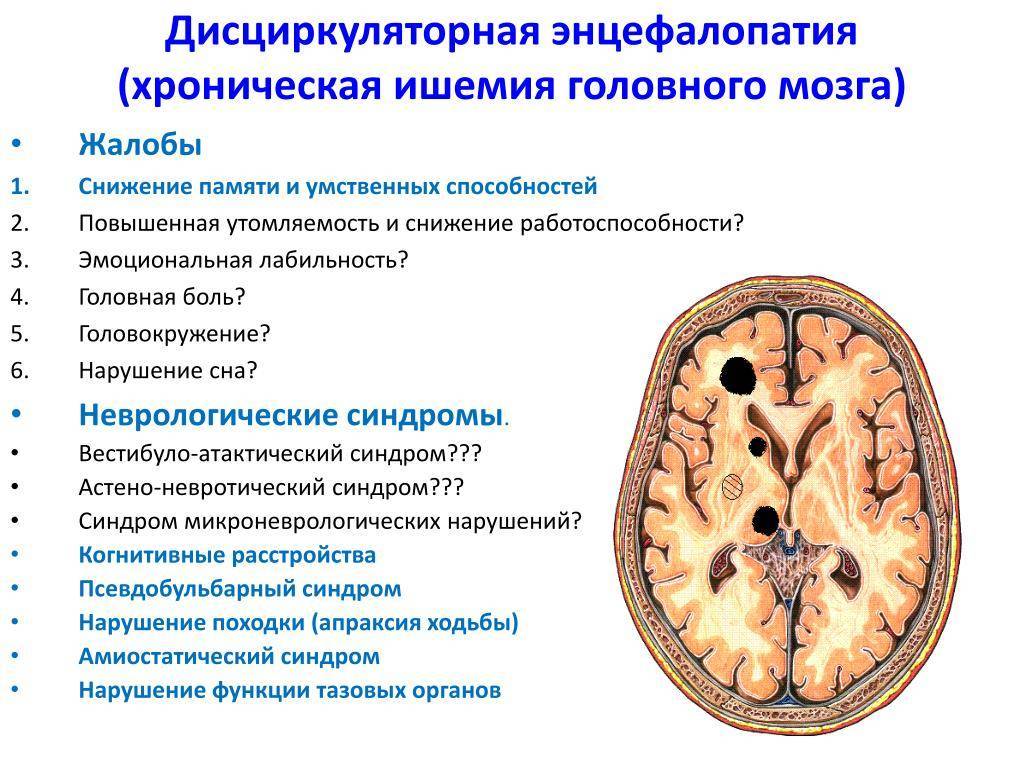

Хроническая ишемия головного мозга и лейкоареоз: симптомы и лечение